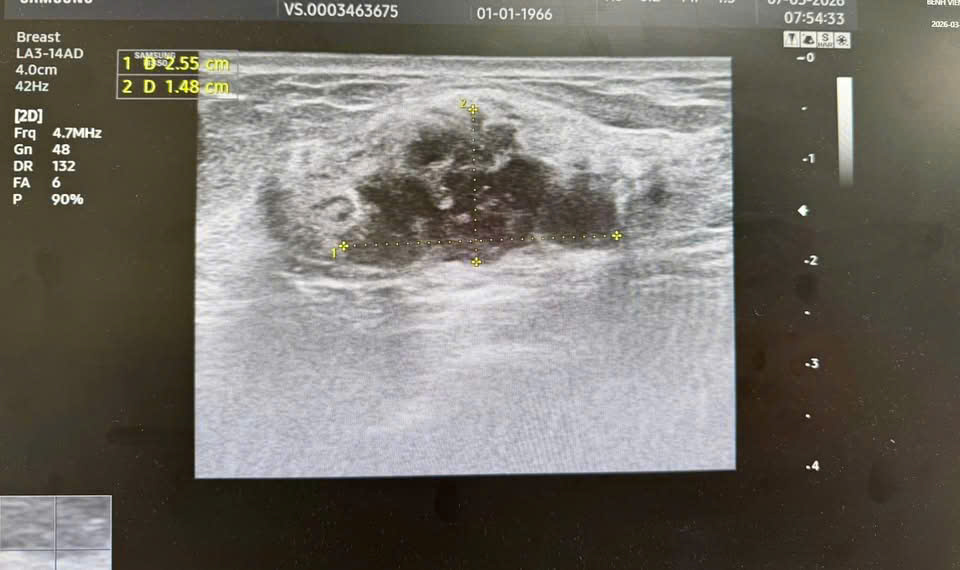

Trong suốt quá trình thăm khám lâm sàng, người bệnh khẳng định bản thân không có bất kỳ triệu chứng bất thường nào. Bác sĩ không sờ thấy khối u, bệnh nhân không cảm thấy đau tức ngực, và vùng da quanh vú cũng không có bất kỳ biểu hiện biến đổi màu sắc hay sần sùi nào. Nếu chỉ đánh giá dựa trên cảm nhận chủ quan và thăm khám bên ngoài, đây là một cơ thể hoàn toàn khỏe mạnh. Tuy nhiên, vỏ bọc khỏe mạnh ấy đã không đánh lừa được hệ thống máy móc chẩn đoán chuyên sâu và kinh nghiệm dày dặn của các chuyên gia chẩn đoán hình ảnh. Thông qua siêu âm và chụp X-quang tuyến vú, các bác sĩ đã phát hiện một dấu hiệu bất thường nằm ẩn sâu bên trong mô tuyến vú. Hình ảnh khối u được phân loại ở mức BIRADS 4, là mức độ cảnh báo có dấu hiệu ác tính. Kết quả xét nghiệm tế bào học (sinh thiết) được tiến hành và đưa ra kết luận cuối cùng: Người bệnh mắc ung thư biểu mô tuyến vú giai đoạn sớm.